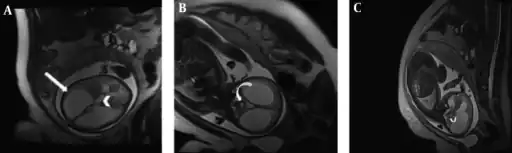

Aqueductal stenosis in a fetus a) Axial b) coronal c) sagittal

Ultrasonography can be used in utero to diagnose aqueductal stenosis by showing dilation of the lateral and third ventricles. A retrospective study found that diagnosis can be made as early as 19 weeks of gestation, and that on average diagnosis is made at 33 weeks.